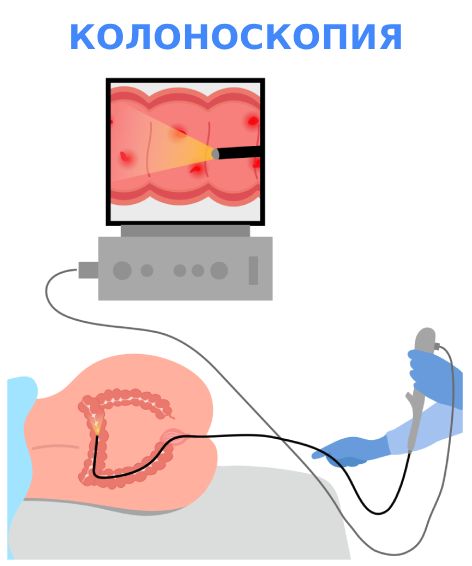

Инструментальные методы

Основные методы, с помощью которых можно обнаружить опухоль в прямой кишке:

- Колоноскопия. Эндоскопическое исследование позволяет визуально осмотреть внутреннюю поверхность толстого кишечника на всём его протяжении. Колоноскопия помогает выявить неоплазию, определить её размеры, положение, макроскопический тип, а также взять биопсию для исследования под микроскопом.

- Ректороманоскопия (ректоскопия). Представляет собой эндоскопическое исследование слизистой прямой кишки, в некоторых случаях — нижних отделов сигмовидной кишки. Позволяет выявить новообразование уже на ранних стадиях.